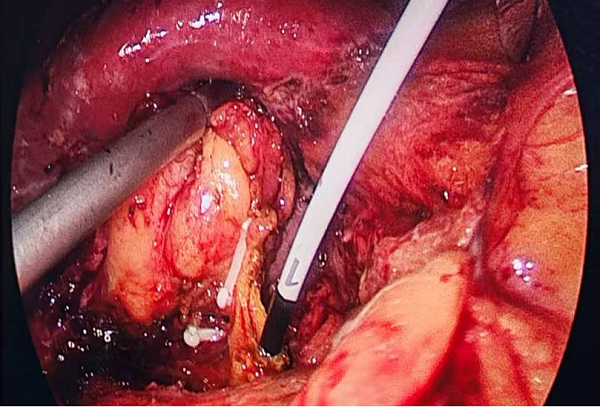

手术中,医疗团队借助直径仅3mm的超细胆道镜,通过胆囊管自然腔道直达胆总管,在不切开胆管、不损伤括约肌的前提下,精准锁定并取出结石。这种“自然腔道+超微器械”的模式,实现了胆囊切除与胆总管取石同步完成,既保留了胆道系统完整性,又避免了留置T管的不便。术后患者24小时即可进食活动,目前患者已康复出院。

术中经胆囊管置入超细胆道镜